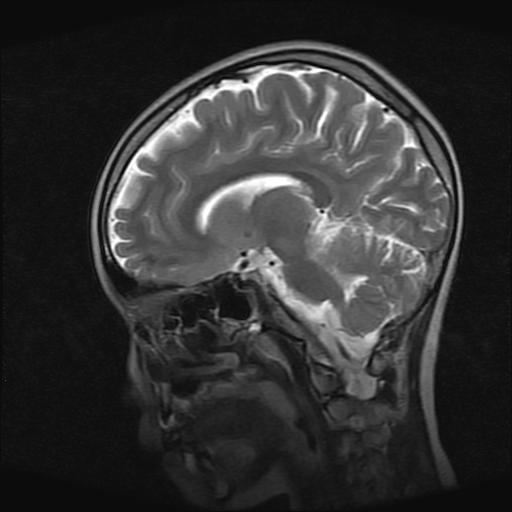

9岁女孩,三岁时诊断为癫痫,一直服丙戊酸钠,现患者一般情况良好,家长复查核磁片,看能否停药..

巨脑回